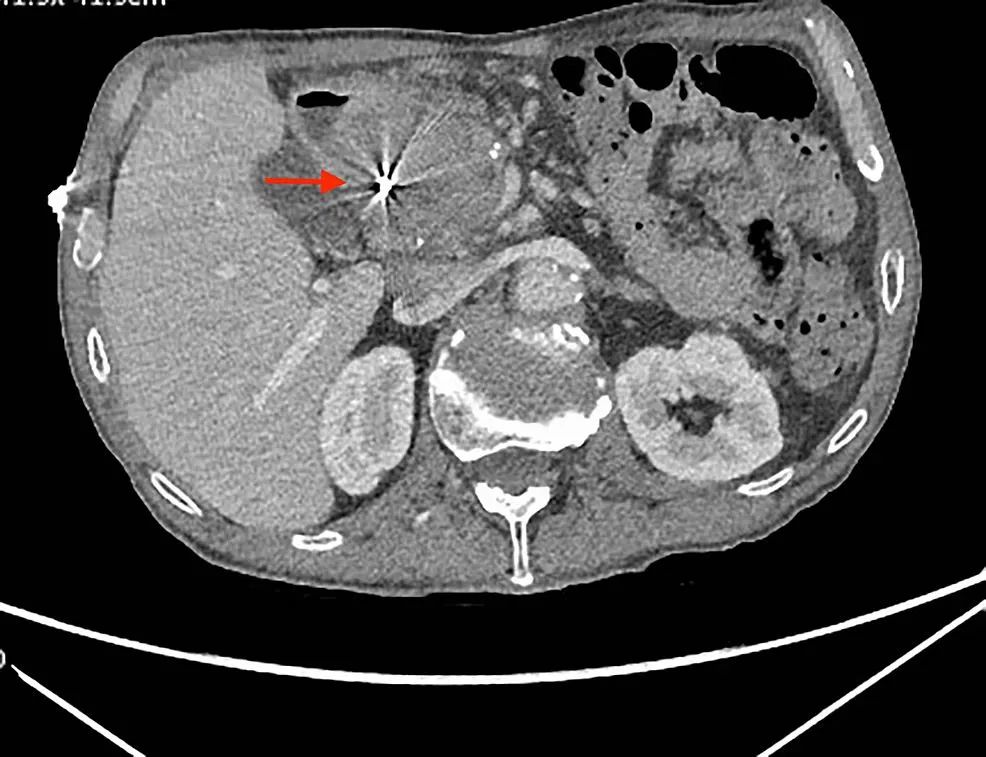

腹部CT显示假性囊肿,大小稳定,但可能经由肠系膜上动脉分支出血。

CT血管造影(CTA),排除了肠系膜上动脉活动性出血,但提示假性囊肿前部出血。

腹腔动脉造影显示一个不规则假性动脉瘤。